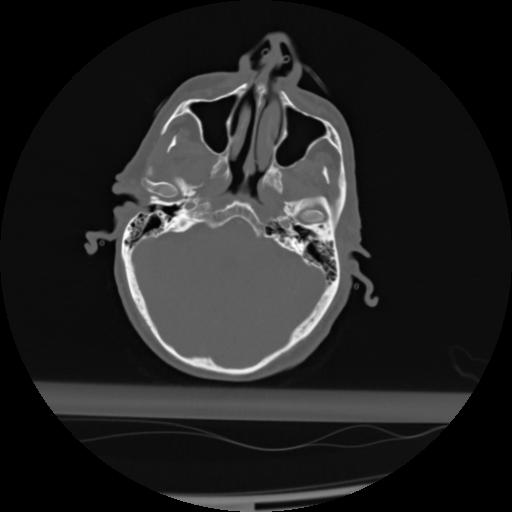

21 ANGIO,CE,Axial,3.0,ANGIO,,